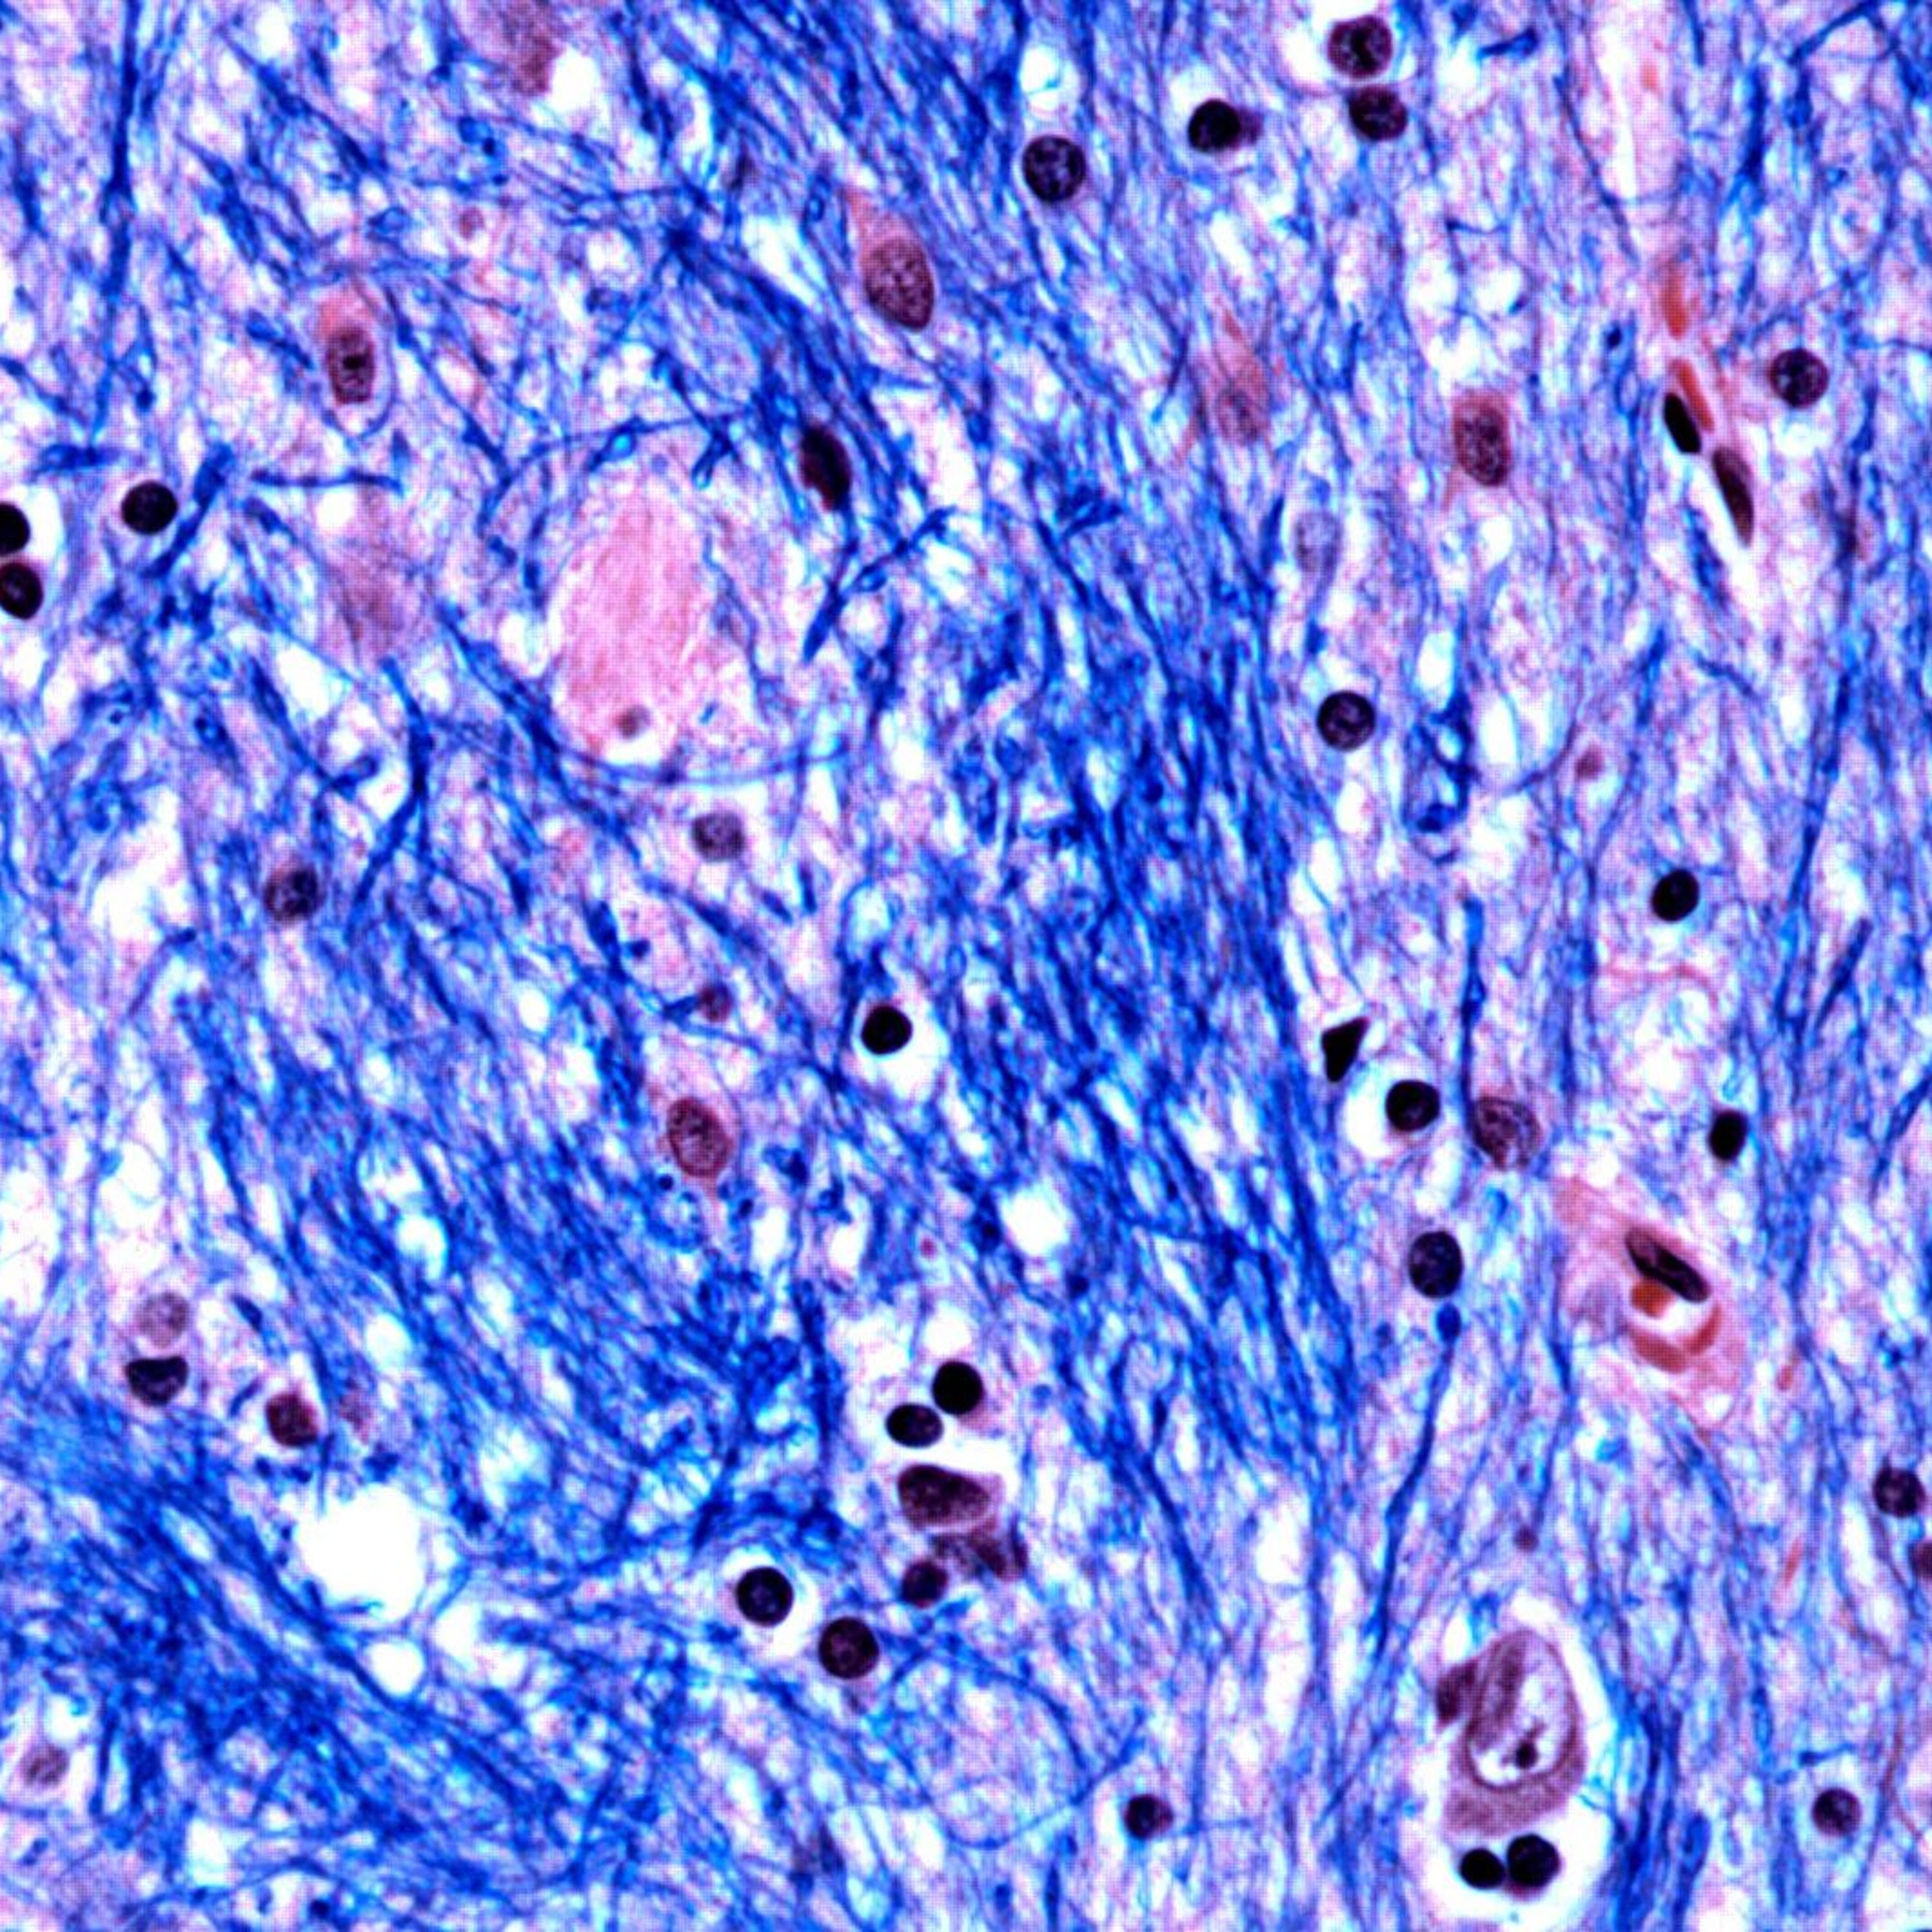

My dad, his ‘incurable’ disease, and hope at last

The Guardian journalist Josh Halliday talks about Huntington’s disease, the impact the rare inherited condition has had on his family and the hope the...